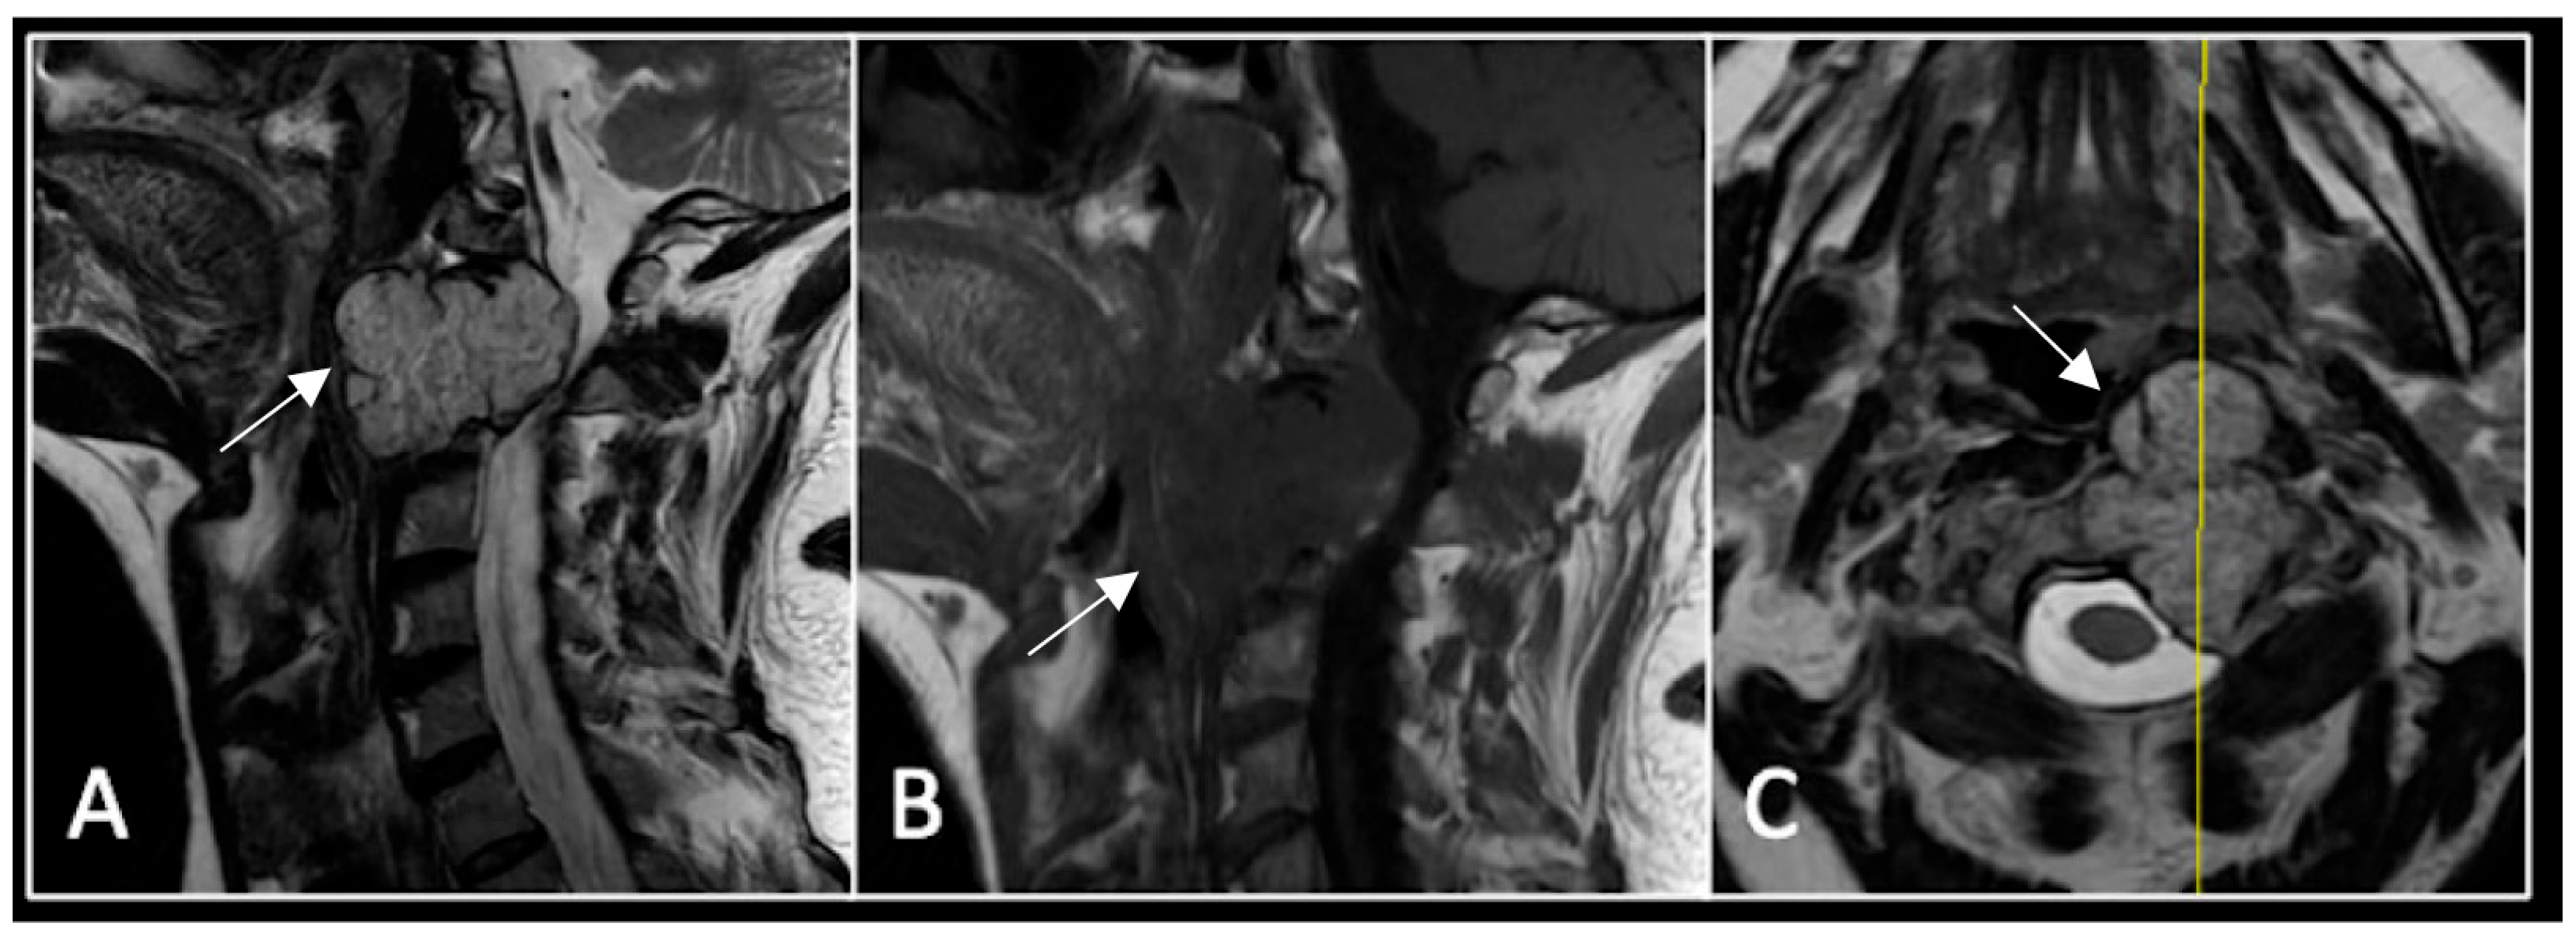

Figure 7.

The MRI demonstrates a left-sided lobular mass (arrow) with invasion of the C2/3 vertebral body and epidural extension, but no cord compression. The yellow line on the axial image indicates the axial slice level. (A) T2W sagittal; (B) T1W sagittal; (C) T2W axial.